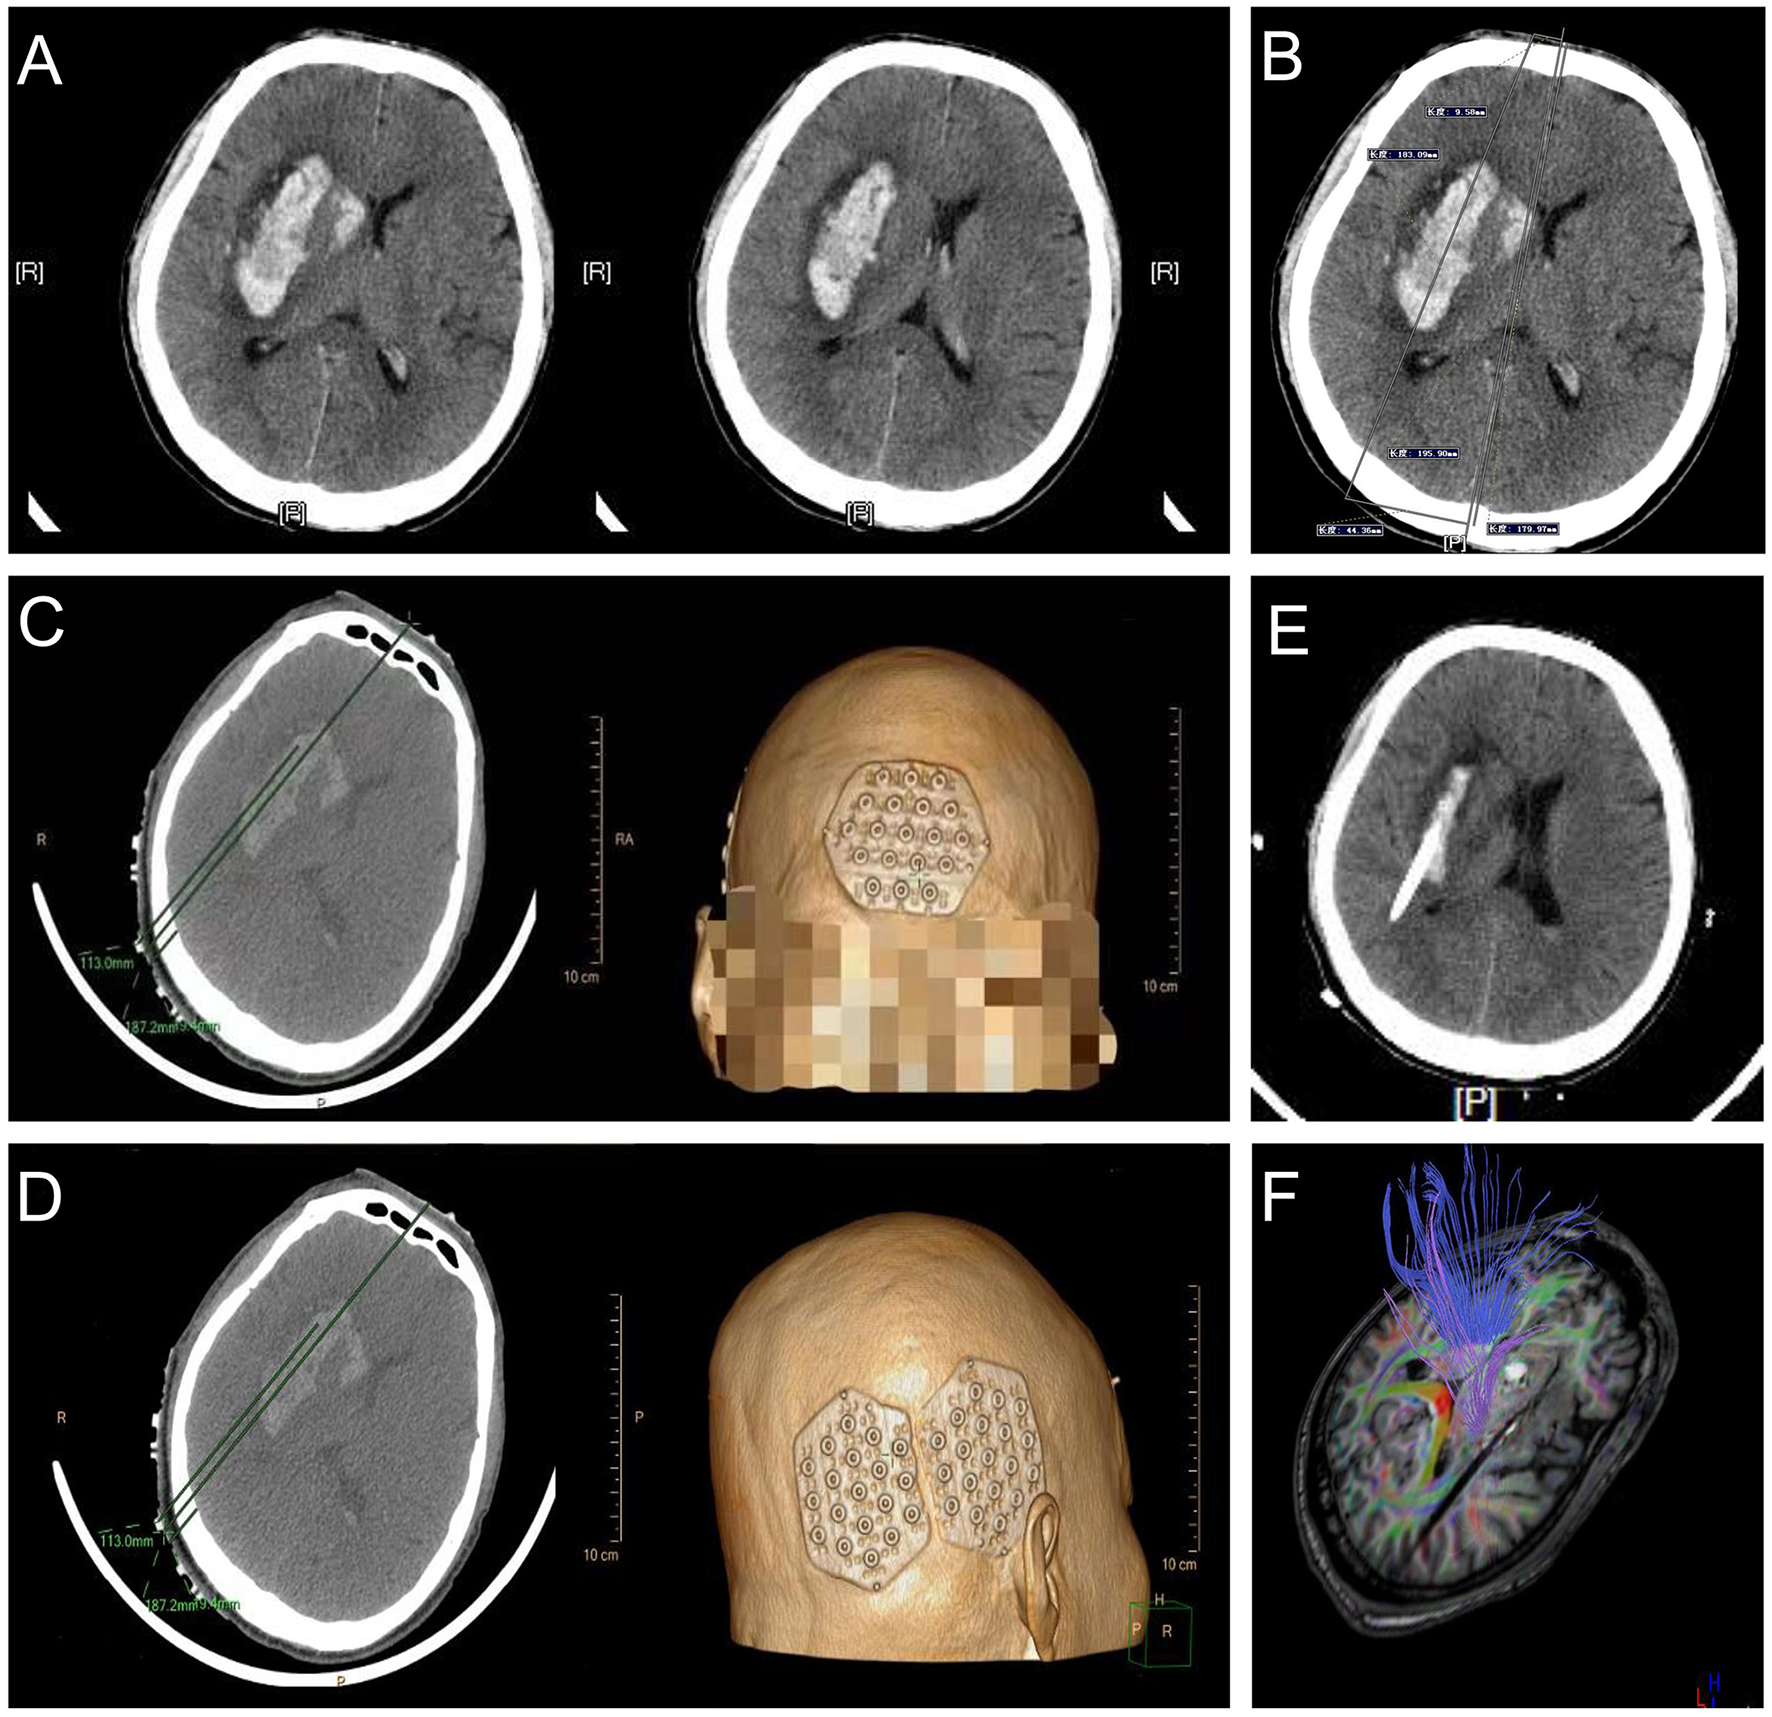

A 54-year-old man with a history of 5 years of hypertension was admitted to our center after a sudden confusion of consciousness and left limb paralysis. Emergency brain CT scans showed a right basal ganglia hemorrhage (Figure 10A). The distance between the orbitomeatal line and an optimal section of the hematoma shown in the CT image was 4.5 cm. Two location stickers were attached on the scalp at a vertical distance of 9.58 mm (reference point) from the centerline and a parallel distance of 179.97 mm (puncture point) along the centerline (Figure 10B). The PISP system (Philips IntelliSearch Portal v5.0.2.10010) was used to show the accurate puncture site, reference point, puncture route, puncture depth (113.0 mm), and drill depth (9.4 mm) by performing a CT scan of 1 mm for each layer before the surgery (Figures 10C,D). Cranial CT conducted the next day revealed the hematoma was almost completely evacuated (Figure 10E). MR diffusion tensor imaging showed that the drainage tube was placed beside the corticospinal tract to remove the hematoma, quickly relieving the pressure on the corticospinal tract, promoting the recovery of the limbs (Figure 10F).

Figure 10

Basal ganglia hemorrhage appears in (A), with a vertical distance of 9.58 mm (reference point) from the centerline and a parallel distance of 179.97 mm (puncture point) along the centerline in (B) used to locate the location sticker in (C,D). (E,F) represent good clinical outcomes.